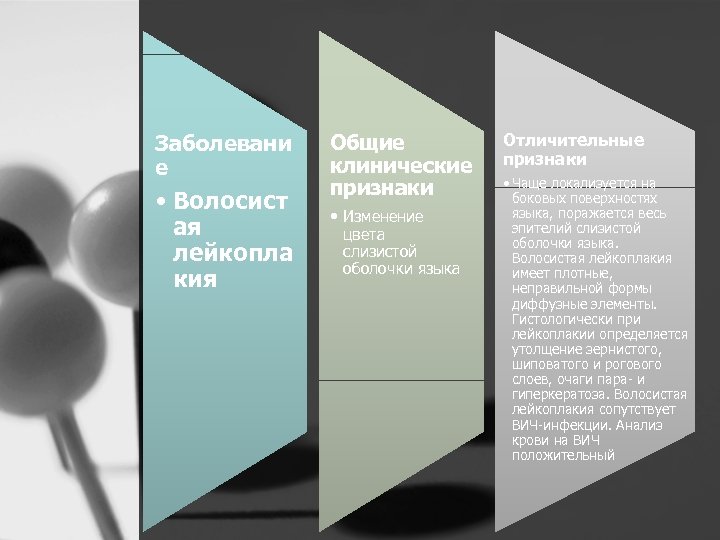

ДИФФЕРЕНЦИАЛЬНАЯ ДИАГНОСТИКА. Заболеван ие • Ложн ый черн ый язык Общие клинические признаки • Изменение цвета слизистой оболочки языка от желтого до темно коричневого и черного Отличительные признаки • Выраженной гиперплазии нитевидных сосочков нет. Все поверхности языка окрашиваются некоторыми пищевыми продуктами или лекарственными веществами (полоскание растворами перманганата калия, хлоргексидина, отваром ромашки и т. д. )

Заболевани е • Волосист ая лейкопла кия Общие клинические признаки • Изменение цвета слизистой оболочки языка Отличительные признаки • Чаще локализуется на боковых поверхностях языка, поражается весь эпителий слизистой оболочки языка. Волосистая лейкоплакия имеет плотные, неправильной формы диффузные элементы. Гистологически при лейкоплакии определяется утолщение зернистого, шиповатого и рогового слоев, очаги пара и гиперкератоза. Волосистая лейкоплакия сопутствует ВИЧ инфекции. Анализ крови на ВИЧ положительный